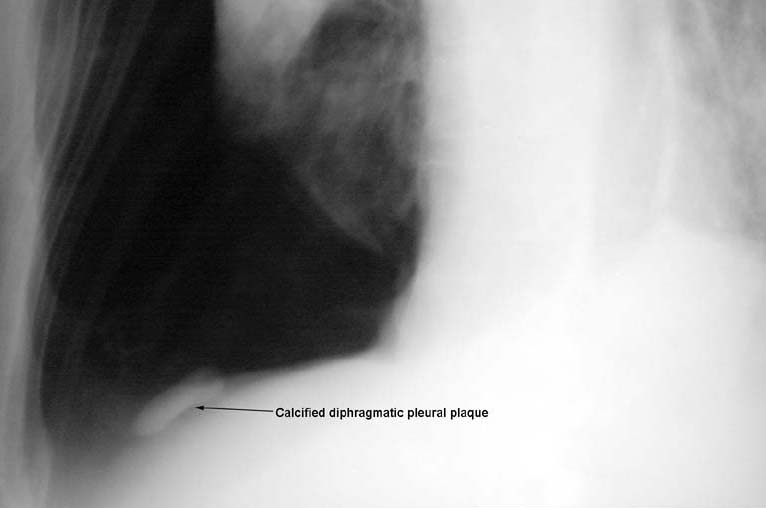

• Calcified diaphragmatic pleural plaque